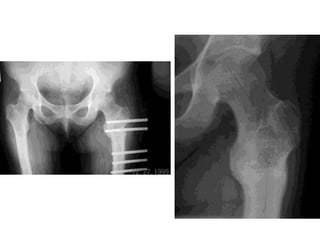

Imaging: X ray

 Initially normal upto 3 months

 Sclerosis

 Flattening

 Subchondral radiolucent lines (lines only seen in x-ray in b

one below the articular cartilage) (cresent sign)

 Collapse of cortex

 OA

Realignment osteotomy

 Used to relocate necrotic area from weight bearing portion

of femoral head

 Angular osteotomies more common

 Multiple techniques for holding the fixation

Imaging: X ray Initially normal upto 3 months  Sclerosis  Flattening  Subchondral radiolucent lines (lines only seen in x-ray in b one below the articular cartilage) (cresent sign)  Collapse of cortex  OA